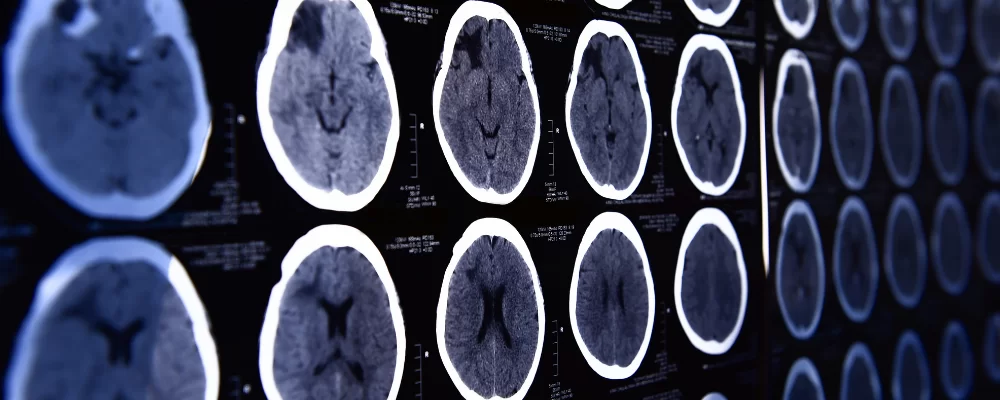

A hemodiafiltração pode aumentar significativamente a depuração de diversos medicamentos, levando a subdosagem quando usamos protocolos baseados em hemodiálise convencional. Entender a farmacocinética da droga e a prescrição da HDF é essencial para evitar falha terapêutica e ajustar corretamente as doses.